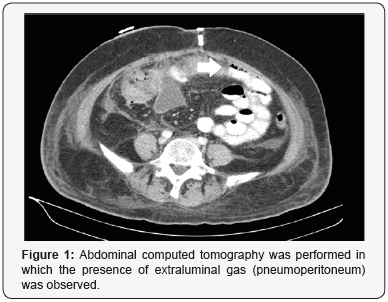

A 65-year-old woman with controlled hypertension, with a history of gynecological surgery: Hysterectomy with adnexectomy, pelvic lymphadenectomy, appendectomy and omentectomy, for uterine body neoplasia (anatomopathological analysis reported Serous Papillary Carcinoma). The patient presented pain and abdominal distension, fever, tachycardia and analytical elevation of acute phase reactants at 36 hours postoperatively. Abdominal computed tomography was performed in which the presence of extraluminal gas (pneumoperitoneum) was observed (Figure 1). We carried out an open approach identifying segmental ischemia of the colon circumscribed to the transverse colon (Figure 2); we carried out resection of this segment and manual anastomosis, favorable postoperative course, with discharge to the 8th day post-reoperation [1-8].

Ischemic lesion of the transverse colon of iatrogenic origin is an infrequent entity, although with a high morbimortality. The radiological test of choice is the abdominal computed tomography (CT), the surgical technique will depend on the intraoperative findings. The presence of this complication is a representative example of the importance of correct identification of anatomical planes between the omentum and the transverse mesocolon, quite possibly the segmental ischemia presented by this patient corresponds to an inadvertent vascular lesion of the middle colic artery.